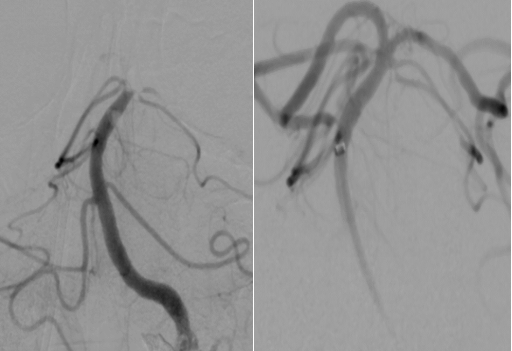

由于患者错过了4.5小时脑卒中静脉溶栓救治时间,无法溶栓治疗。郝永岗副主任带领神经血管介入团队评估病情后决定在全麻下为患者实施动脉取栓术,挽救处在缺血状态尚未坏死的脑组织。麻醉科李健主任第一时间到达导管室,保障手术顺利进行,术中可见患者基底动脉末端闭塞(基底动脉尖综合征)。医生运用SWIM技术取出黑红色血栓,复查造影显示:基底动脉远端血流通畅,双侧大脑后动脉、小脑上动脉显影。术中发现患者左侧椎动脉起始部重度狭窄,于病变处植入支架一枚,血管狭窄解除,术后送重症医学科继续治疗。